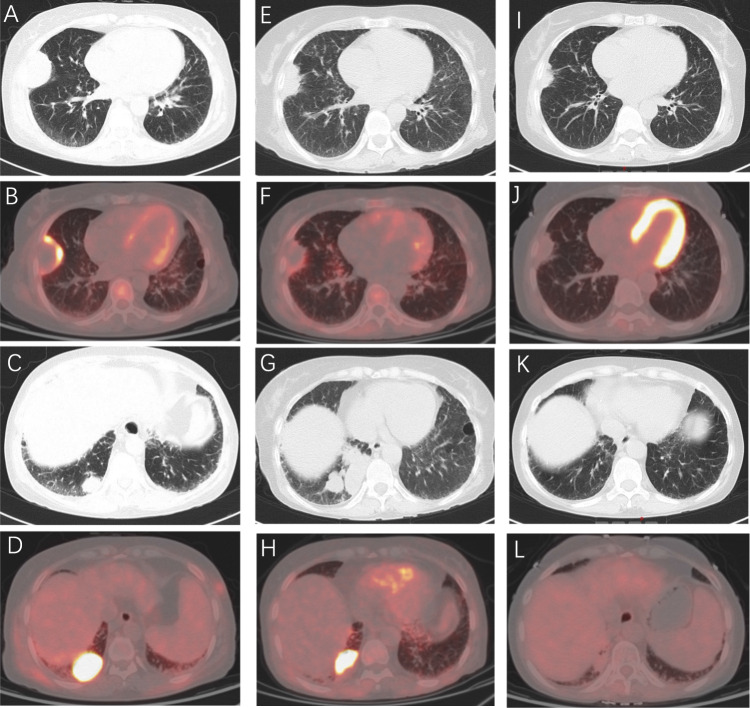

Glofitamab是一种CD20×CD3 t细胞结合双特异性单克隆抗体,已成为复发/难治性b细胞非霍奇金淋巴瘤的治疗药物。嵌合抗原受体t细胞疗法和t细胞参与双特异性抗体的出现也激发了人们对其在自身免疫性疾病中的潜在应用的兴趣。在这里,我们报告一例弥漫性大b细胞淋巴瘤(DLBCL),患者有长期的抗合成酶综合征(ASyS)病史。患者在一线R-CHOP和二线polatuzumab vedotin联合来那度胺治疗失败后,接受三线格非他单抗治疗,淋巴瘤完全缓解。值得注意的是,她的ASyS症状在多种免疫抑制剂(环孢素、甲氨蝶呤、羟氯喹)和靶向治疗(托法替尼、巴西替尼)后也得到了缓解。该病例强调了格非他单抗不仅作为难治性DLBCL的有效治疗,而且作为伴随自身免疫性表现的一种新的治疗策略的潜力,值得在自身免疫性疾病的背景下进一步研究。